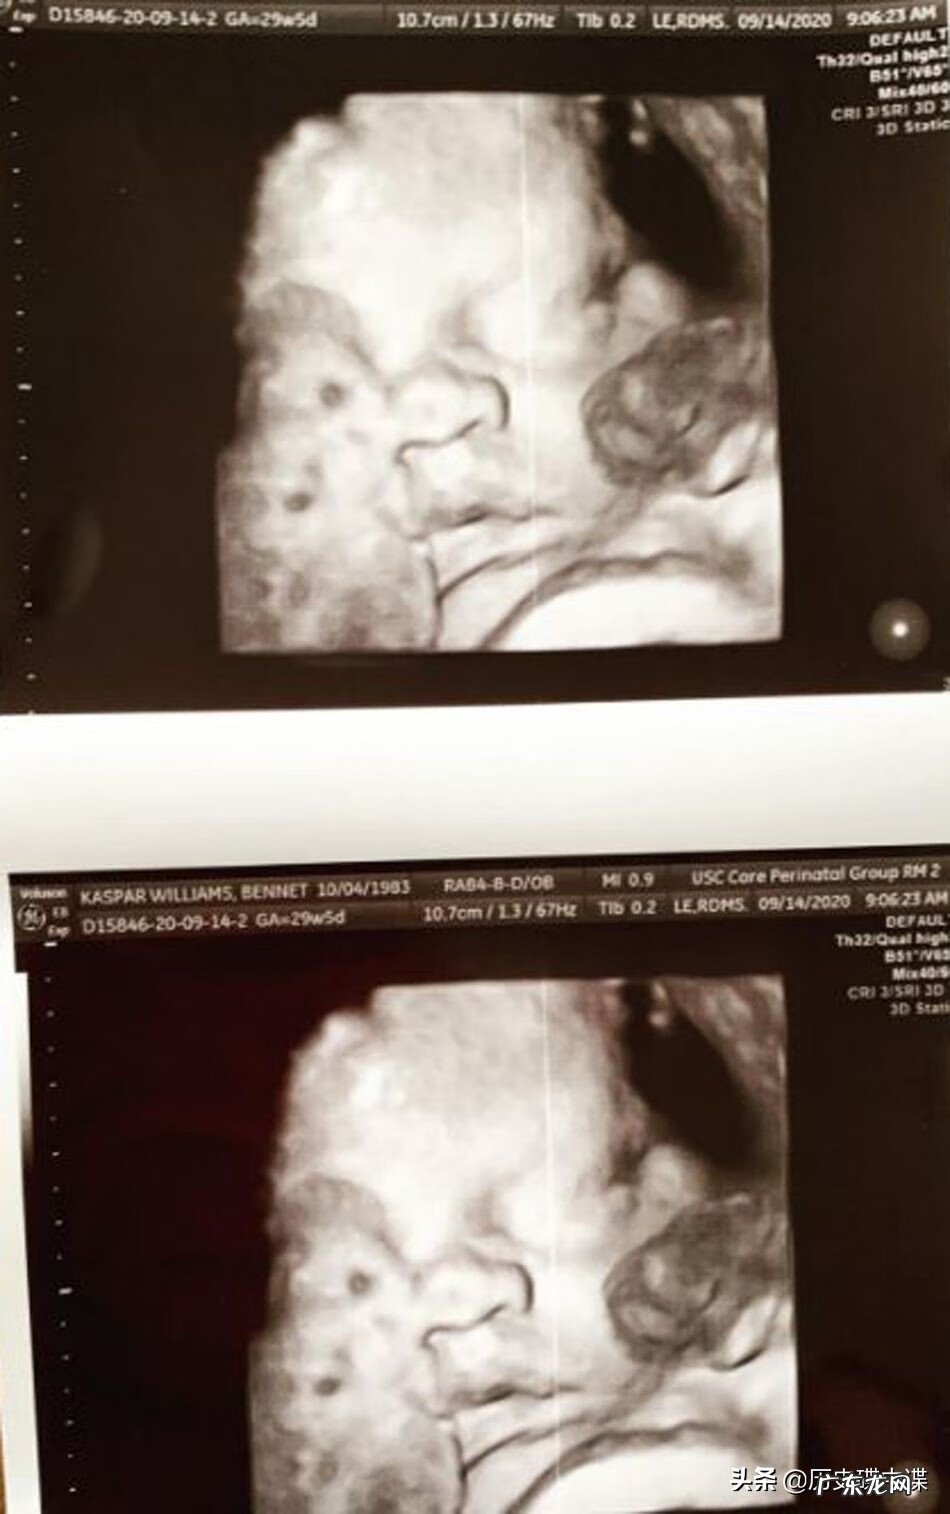

怀孕期间贝尔特的产检图像 , 宝宝十分健康